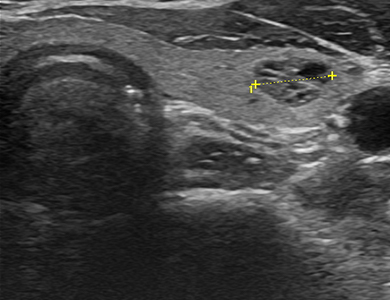

ÃÊÀ½ÆÄ »çÁø

¿ìÃø Á¤»ó °©»ó¼±

img

ÁÂÃø Á¤»ó °©»ó¼±

Á¤»ó °©»ó¼± ÇùºÎ